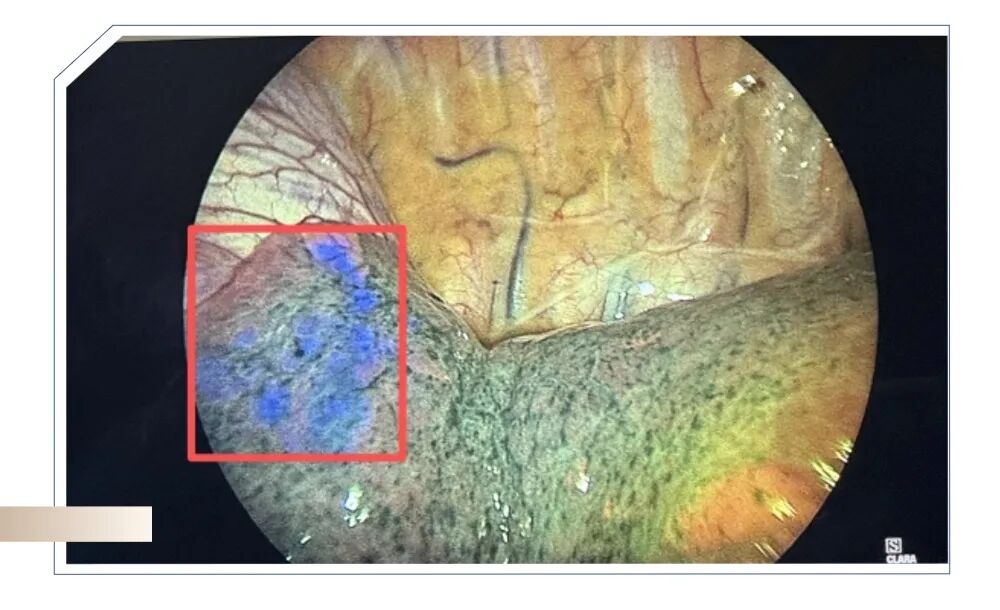

5G 远程技术为核心支撑,本次手术创新性地实现了医生与手术室的远程联动。在远程控制端,韩丁培主任通过远程操控机器人系统,实时操作手柄,精准地将导航镜引导抵达病灶所在气道;在手术室端,助手王心怡医师在超视距操作模式,依次完成了右肺上叶结节胸膜下的“点状”定位、右肺下叶结节胸膜下的“面状”定位以及双病灶染色操作。手术过程中,远程手术机器人展现出了全程稳定精准的特点,尤其在对病灶实现“深度到达”方面表现卓越。最终,手术团队成功完整切除了目标病灶,为后续的临床治疗提供了可靠的依据。